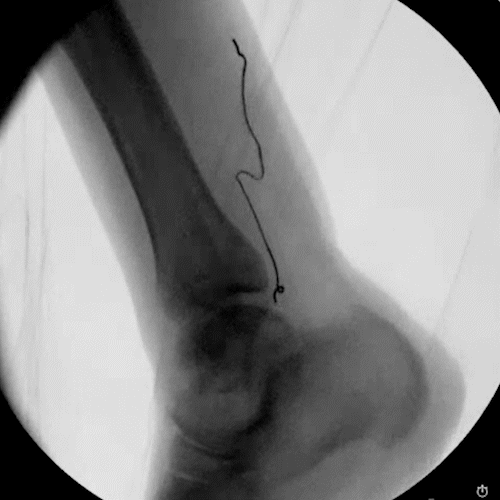

Ultrasound & Fluoroscopy Visualization

Placement is everything in neuromodulation, which is why device visualization is key. The Injectrode appears hyperechoic under ultrasound and displays a large acoustic shadow, allowing for clear imaging during placement. The device can also be readily imaged with fluoroscopy.